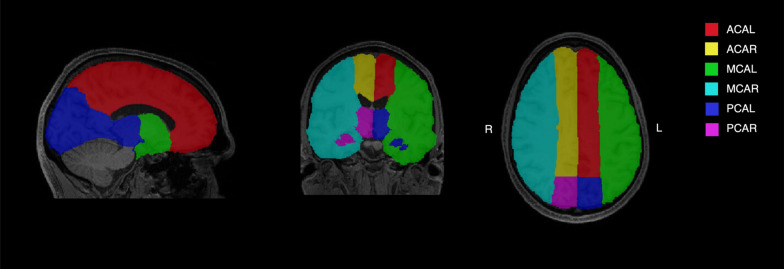

神经血管单元中的液体运输通过营养输送和废物清除对维持大脑健康至关重要。然而,这些系统是复杂的,这些系统元素之间的相互依赖关系以及它们如何随着年龄的增长而变化还没有得到很好的理解。MRI结果可以深入了解这些系统在体内的潜在生物学机制,包括通过神经血管单位的水交换率(BBB kw)、血管周围空间扩大(ePVS)、脑血流量(CBF)、游离水(FW)和白质高信号(WMH)。为了探索神经血管单元功能元素之间的关系,本研究使用贝叶斯混合模型研究了这些MRI测量之间的关系,以及它们随实足年龄或脑萎缩相关年龄(brainageR)的变化,使用线性回归。132例非临床老年人(平均年龄67岁;68%女性),BBB kw与CBF呈正相关(β^ = 0.08, 95%可信区间(CI) =[0.02, 0.15])。弗兰克-威廉姆斯积极与ePVS(β^ = 0.44,CI =[0.30, 0.63])和负责人(β^ = 0.13,CI =[0.04, 0.21])。BBB kw、CBF和ePVS随年龄的增长而降低,FW和WMH随年龄的增长而增加(均p 0.05)。FW、ePVS和WMH之间的关系可能反映了不同隔室内流体调节的互联性,而BBB kw和CBF之间的关系表明了神经血管流体流动和血管功能之间的联系。虽然神经血管完整性的个体指标与年龄有关,但它们之间的相互关系似乎是稳定的,这为未来研究神经退行性疾病中的液体输送和血管健康提供了基线。

Fluid transport in the neurovascular unit is essential for maintaining brain health through nutrient delivery and waste clearance. However, these systems are complex and the inter-dependencies between elements of these systems and how they may change through aging is not well understood. MRI outcomes provide insight into the underlying biological mechanisms of these systems in vivo, including water exchange rate through the neurovascular unit (BBB kw), enlarged perivascular spaces (ePVS), cerebral blood flow (CBF), free water (FW), and white matter hyperintensities (WMH). To explore the relationships between functional elements of the neurovascular unit, this study investigated relationships between these MRI measures using Bayesian mixed models, and their variation with chronological age or atrophy-related brain age (brainageR) using linear regression. In 132 non-clinical older adults (mean age = 67 years; 68% female), BBB kw positively associated with CBF (β^ = 0.08, 95% credible interval (CI) = [0.02, 0.15]). FW positively associated with both ePVS (β^ = 0.44, CI = [0.30, 0.63]) and WMH (β^ = 0.13, CI = [0.04, 0.21]). BBB kw, CBF and ePVS decreased with age, while FW and WMH increased (all p < 0.05). There were no associations with atrophy-related brain age (all p > 0.05). Relationships between FW, ePVS and WMH likely reflect interconnectivity of fluid regulation within different compartments, while the relationship between BBB kw and CBF indicates a link between neurovascular fluid flow and vessel function. While individual metrics of neurovascular integrity are associated with age, their inter-relationships appear stable, providing a baseline for future research in fluid transport and vascular health in neurodegenerative disease.